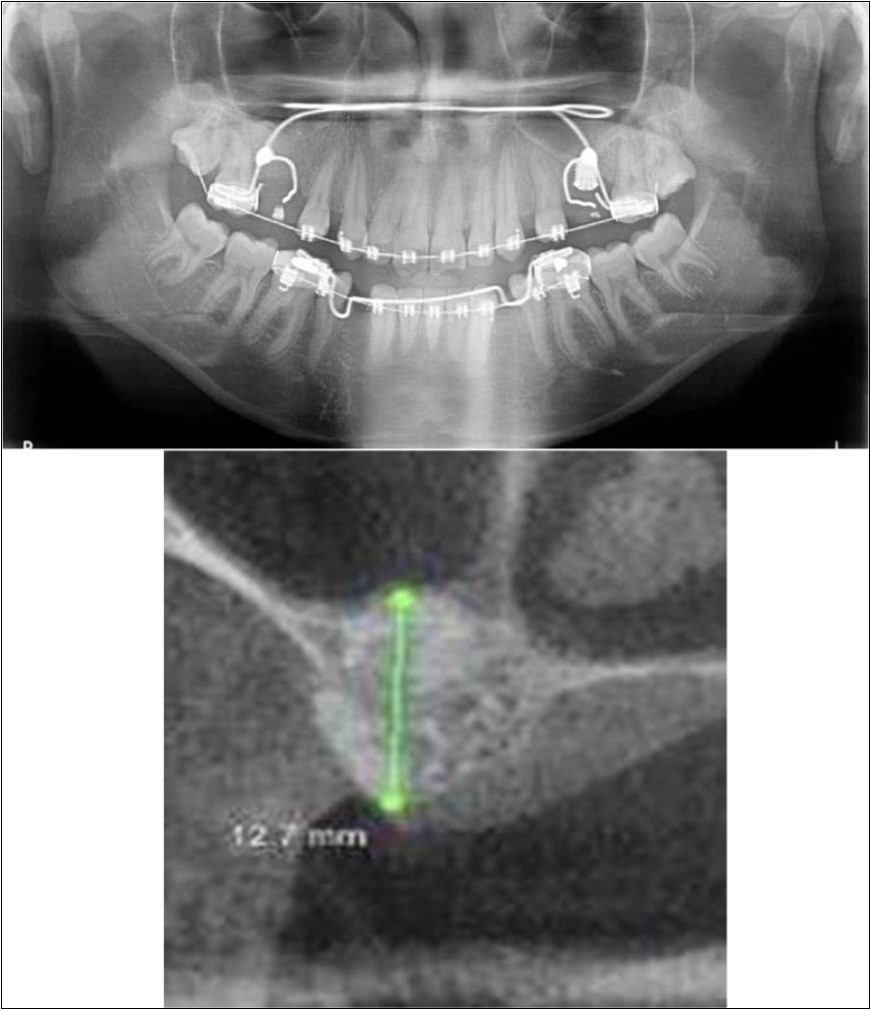

Case Report 5:

A 63 years old male patient reported to the Department of Oral and Maxillofacial Surgery, D.A.P.M.R.V Dental College and Hospital seeking options for implant prosthesis for replacement of missing teeth in upper left back tooth region. The teeth were extracted two years ago because of extensive caries and failure of root canal treated 26, 27. No prosthetic rehabilitation was carried-out in the past. Patient was a known case of diabetes mellitus since 20 years which was under control and was on medication for the same. His general health was satisfactory with no other co-morbidities. Patient did not give history of any existing sinus pathologies.

Clinical and Radiological Assessment:

1.Partially edentulous maxillary arch with missing 24, 25, 26, 27, 28;

2.Increased pneumatisation of left maxillary sinus;

3.Height of available bone- 2.5mm;

4.Transverse thickness of available bone (CBCT evaluation)- 10.9mm;

5.Inter-ridge space adequate to place implant (12mm).

Treatment:

Patient underwent the procedure of direct sinus elevation using sinus lateral approach kit. After crestal and vertical release incisions, muco-periosteal flap was raised to expose the buttress region. A bony window of 1cm diameter was created; sinus lining identified and elevated up to receive calcium phosphosilicate as graft material and closure was achieved under local anaesthesia and strict aseptic protocols. Implant placement was planned to be carried-out after a period of 6 months to allow for the consolidation for graft and naive bone formation. At the end of 6 months, a repeat CBCT scan was advised to evaluate the increase in bone height. (Figure 15a,b, pre-treatment; Figure 16a,b, post-treatment)

Figure 15.a,b. Pre-treatment OPG and cross section of CBCT showing residual alveolar bone height for Case No.5;

Figure 16.a,b. Post-treatment OPG and cross section of CBCT showing residual alveolar bone height for Case No.5;